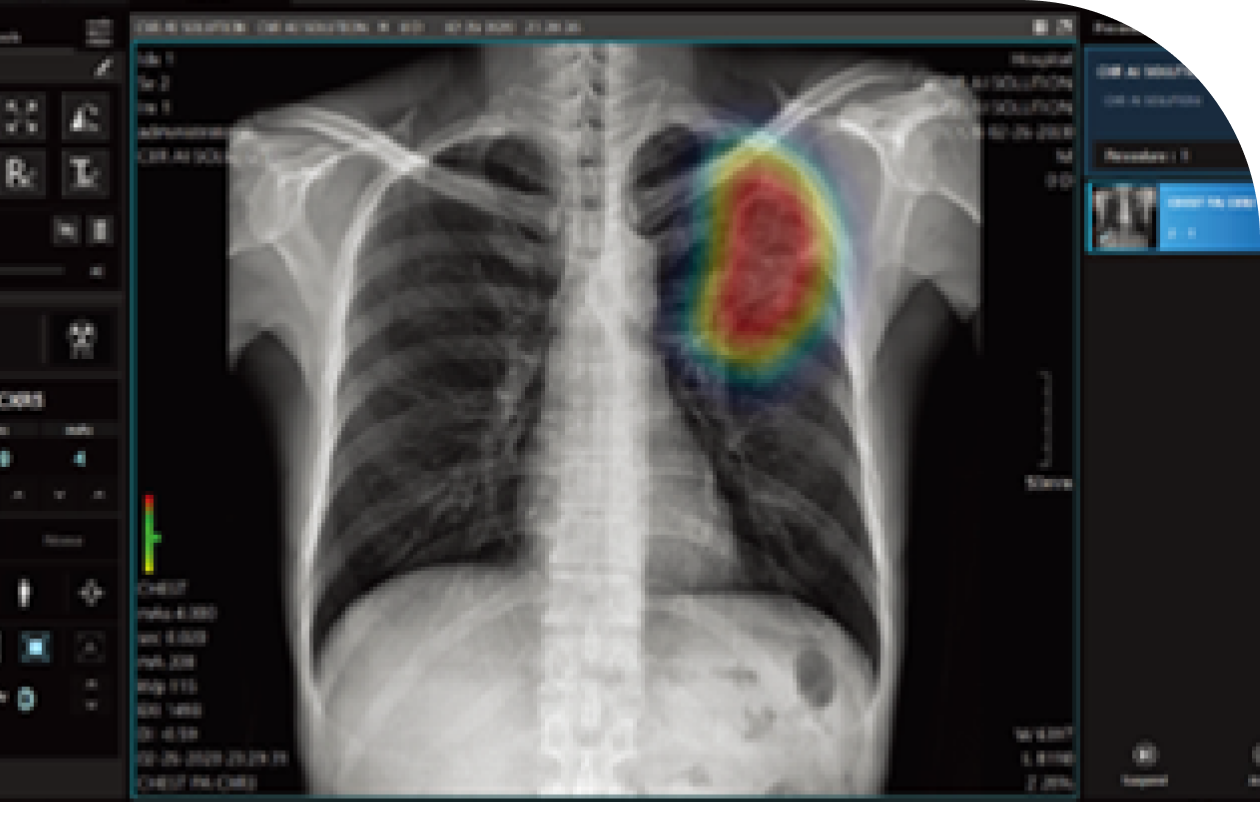

흉부 X선 사진

흉부X선 사진을 통한

흉부 구조와 심폐 이상 여부를 정확히 확인하는 것

• 심장, 폐, 혈관 등 흉부 장기의 구조적 이상과 질환 여부를 평가하기 위해 시행

• 가슴 부위를 X선 장치로 촬영하여 영상으로 확인하는 검사